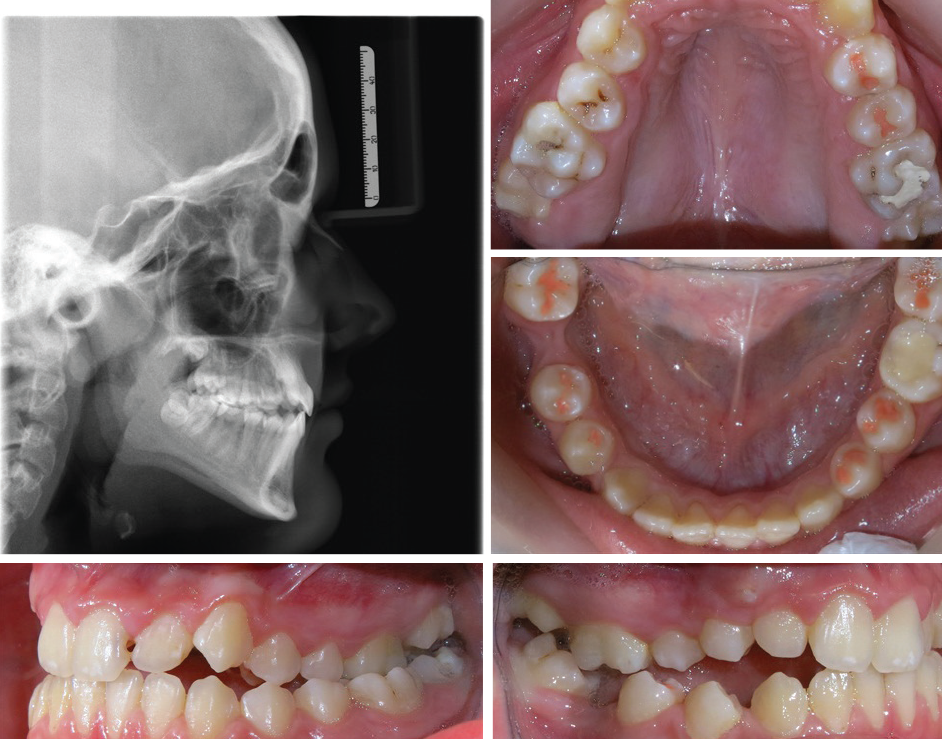

Class III Case with Lost Space for Upper Canine - Treatment Options

Class III Case with Lost Space for Upper Canine— Treatment Options

Before this Townie starts treatment, he asks for advice on how to proceed.